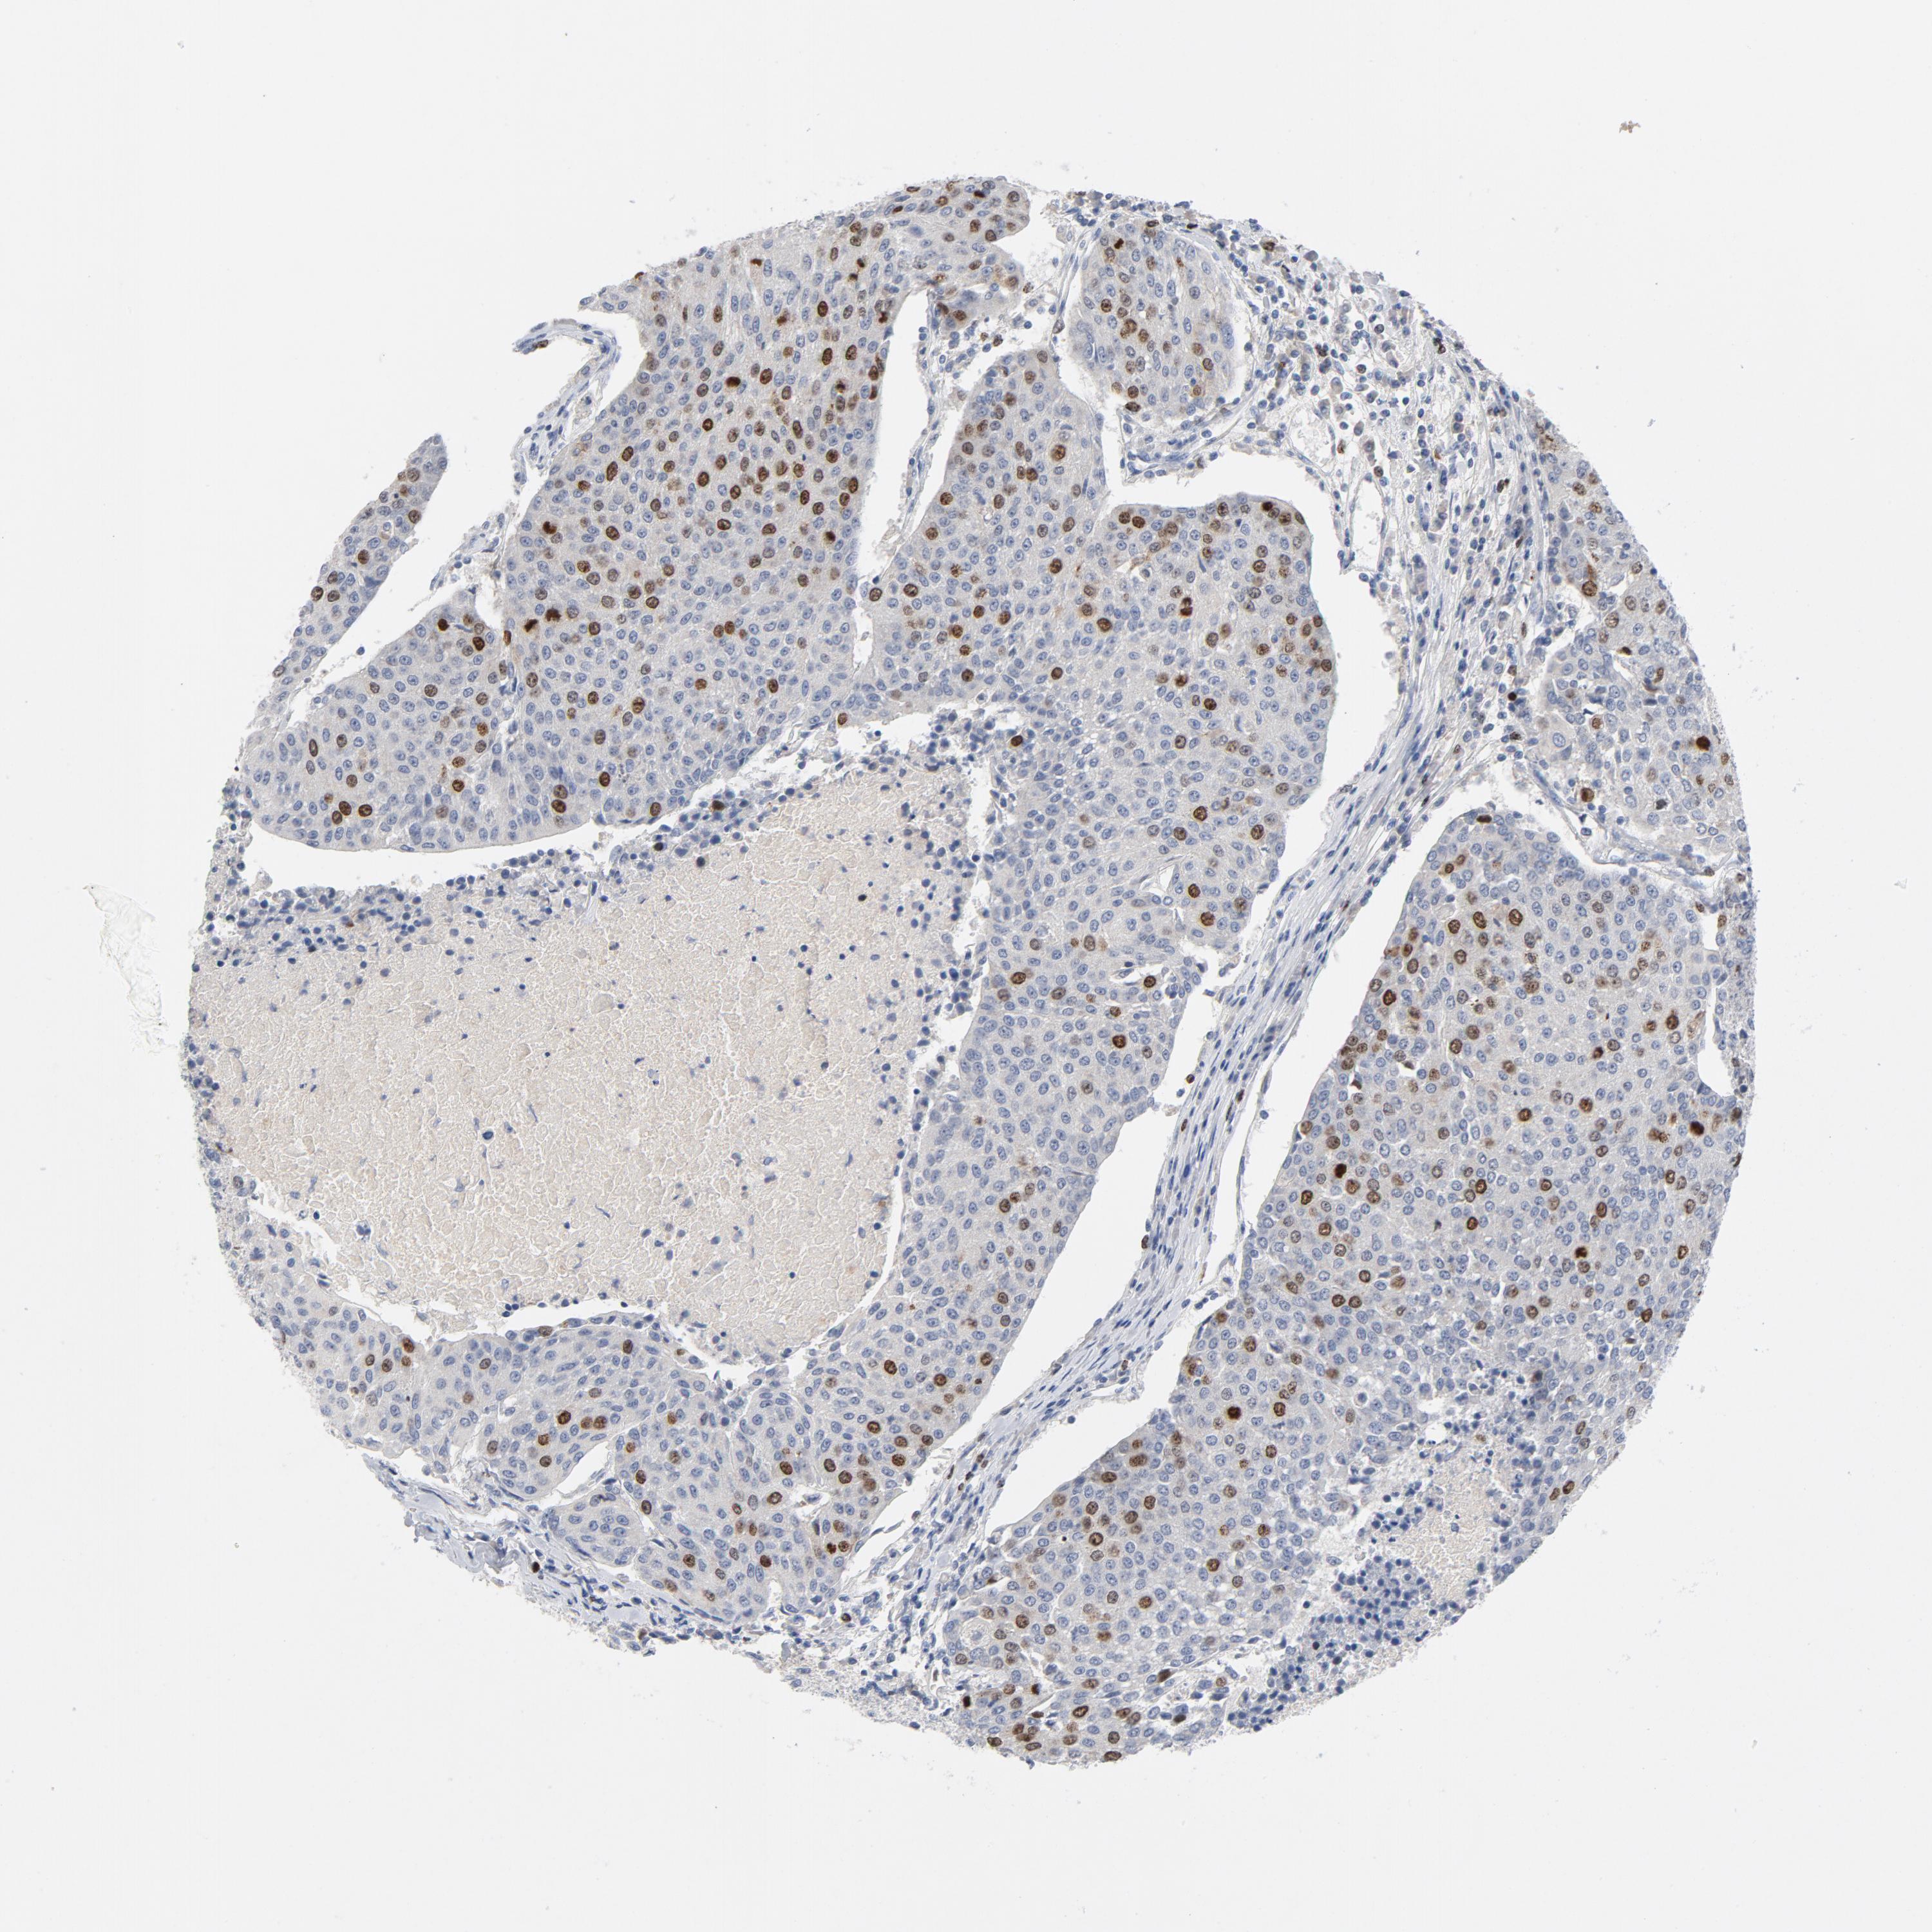

UROTHELIAL CANCER - Protein expressioni

A mouse-over function shows sample information and annotation data. Click on an image to view it in a full screen mode. Samples can be filtered based on level of antibody staining by selecting one or several of the following categories: high, medium, low and not detected. The assay and annotation is described here.

Note that samples used for immunohistochemistry by the Human Protein Atlas do not correspond to samples in the TCGA dataset.

Antibody stainingi

Antibody staining in the annotated cell types in the current human tissue is reported as not detected, low, medium, or high, based on conventional immunohistochemistry profiling in selected tissues. This score is based on the combination of the staining intensity and fraction of stained cells.

Each image is clickable and will lead to virtual microscopy that enables deeper exploration of all samples and also displays staining intensity scores, fraction scores and subcellular localization as well as patient and tissue information for each sample.

Antibody HPA002830

Antibody CAB004270

Staining

High

Medium

Low

Not detected

Intensity

Strong

Moderate

Weak

Negative

Quantity

>75%

75%-25%

<25%

None

Location

Nuclear

Cytoplasmic/membranous

Cytoplasmic/membranous,nuclear

Urothelial carcinoma, High grade

Urothelial carcinoma, Low grade